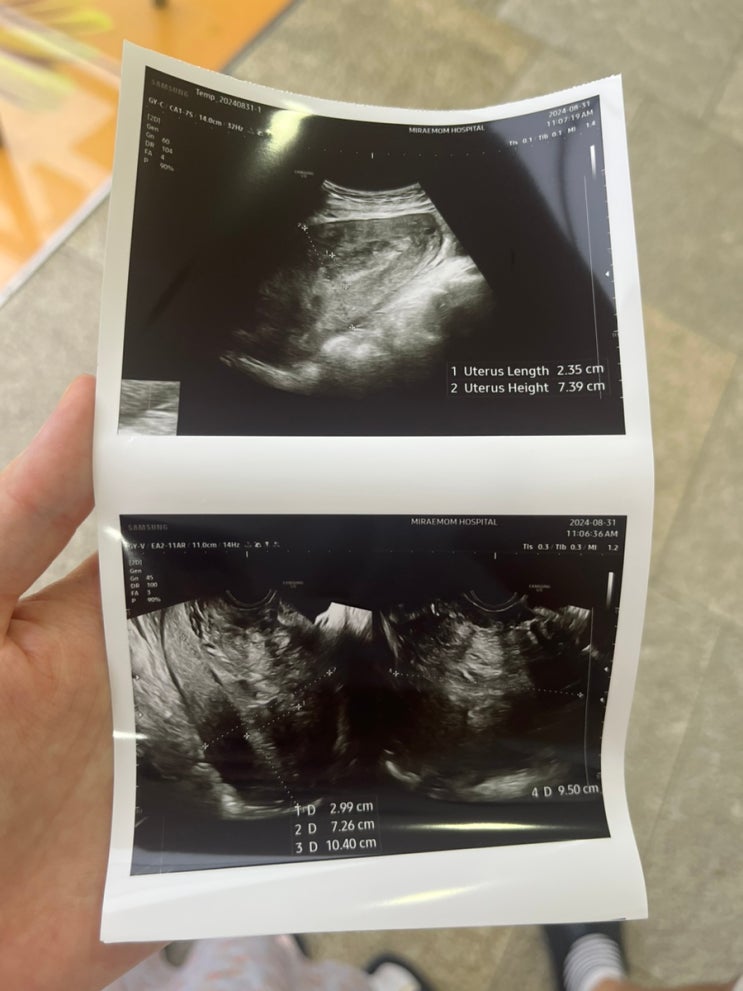

출산후 폭풍 하혈, 자궁수축제 맞은 후기

출산후 폭풍 하혈을 하다 병원에서 퇴원 후 조리원 라이프에 적응해갈때쯤, 출산 후 9일째가 되던 날이었다...